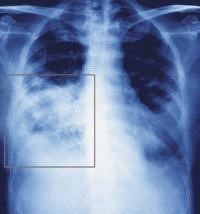

Боль в правом боку в районе подреберья – это симптом многих заболеваний органов брюшной полости. В районе правого подреберья расположен желчный пузырь, головка поджелудочной железы, часть двенадцатиперстной, тонкой и ободочной кишки. Болезни печени, почек тоже проявляются болезненностью в той же области.

Боль справа сзади со спины чаще развивается при дегенеративных изменениях позвоночника, остром холецистите, заболеваниях легких, почек, желудочно-кишечного тракта или других потенциально опасных болезнях.

Если у вас появились боли в спине выше поясницы справа, то скорее всего они возникают по причине нарушения нормального функционирования внутренних органов – как ЖКТ, так и мочеполовой системы. При такой локализации боли принято сначала предполагать заболевания желчного пузыря, камни в почках или радикулит.

Болезни печени, воспаление аппендикса, патология правой почки, паховая грыжа, воспаление придатков матки, заболевания поджелудочной железы, заворот кишок.